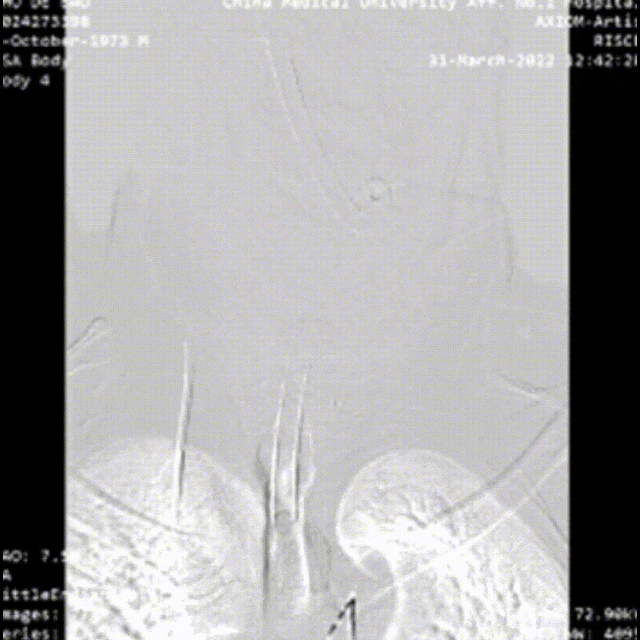

48岁男性,胸腹痛20小时,右下肢一过性麻木,TEVAR治疗

夹层累及股动脉(支架入路),需要参考术前CT,在彩超引导下穿刺入真腔,或者行股动脉剖开,直视下辨认真假腔。